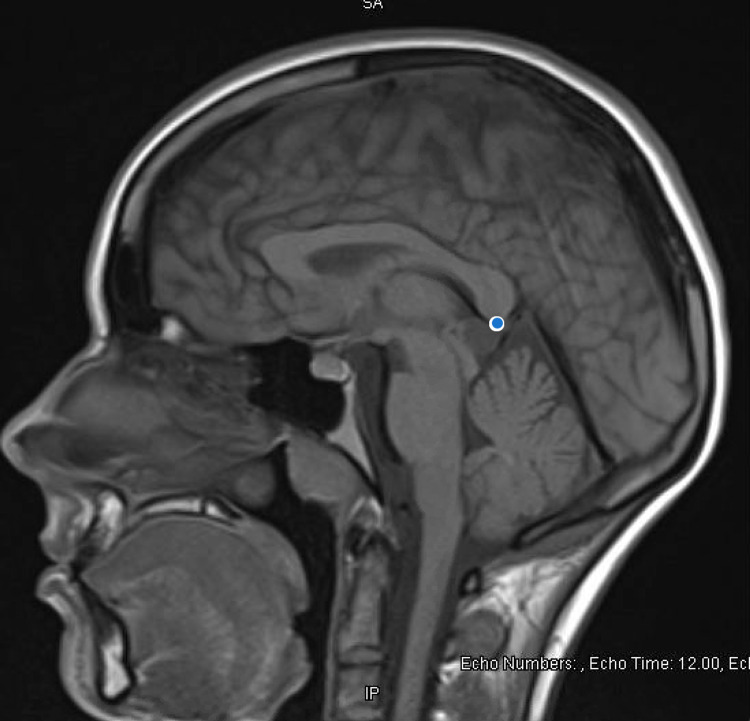

Extensive organic workup was pursued for first break psychosis with initial higher suspicion for organic etiology given unexplained hypertension, prompting concern for anti-N-methyl D-aspartate (anti-NMDA) receptor encephalitis. HIV Ag/Ab screen, NMDA IgG, vitamin D, folate, vitamin B6, B12, B1, heavy metal profile, phosphorus, and magnesium levels were all normal. Table 1 summarizes labs pertinent to our investigation. Brain imaging mentioned previously (CT of the head) was negative for intracranial pathology. An MRI of the brain (see Figure 1) was obtained, which was notable for pineal gland cyst and occipital venous anomaly, determined to be incidental after consultation with neurosurgery.

During our patient’s admission, she underwent brain imaging (MRI) which revealed the pineal gland cyst. The lesion was described as "hyperintense, measuring 1.3 cm x 1.3 cm." Our patient was also found to have an occipital venous anomaly, but the remainder of the imaging was normal. Her previous CT head depicted normal brain white matter, no mass effect, and no hemorrhage. Neurosurgery was consulted, due to her MRI findings, to assess if these rather incidental findings could explain our patient’s first presentation of psychosis. Our patient of study also developed unexplained hypertension (which could indicate a form of endocrine dysfunction, which pineal gland dysfunction is known to cause). Neurosurgery’s impression was that the findings were incidental but suggested that a repeat brain MRI in three-six months was required to follow up on the cyst.